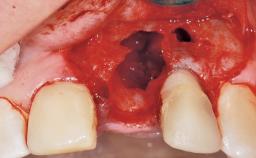

A 39-year-old male patient presented with a chief complaint of discomfort and gingival discoloration around his maxillary left central incisor. He was in good general health and was a non-smoker. His past dental history was significant because of the traumatic fracture of tooth 21 in a sporting accident at age 13. Initial dental treatment included endodontic therapy and a full-coverage restoration. The patient became symptomatic 5 years later, when structural failure of the tooth resulted in the dislodgment of the crown. Endodontic retreatment, apical surgery, and post-and-core restoration were performed.

Bone Volume Deficient horizontally, requiring prior grafting